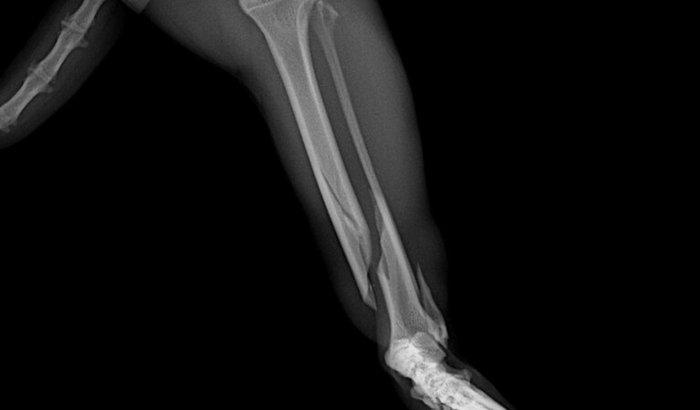

Ele sofreu uma fratura na tíbia, e o raio-X mostrou que ele vai precisar passar por uma cirurgia ortopédica de urgência com pino e placa para recuperar a patinha.

O Kiran está sentindo dor e não consegue andar e sem a cirurgia, ele pode perder a mobilidade e tem a possibilidade de ter que amputar a pata.

🩻 A imagem do raio-X está aqui na vaquinha para mostrar exatamente a gravidade da fratura.